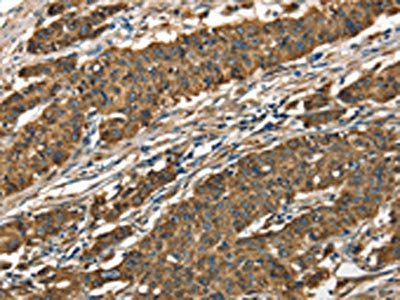

The image on the left is immunohistochemistry of paraffin-embedded Human gastic cancer tissue using CSB-PA296813(CTSE Antibody) at dilution 1/40, on the right is treated with fusion protein. (Original magnification: ×200)

The image on the left is immunohistochemistry of paraffin-embedded Human thyroid cancer tissue using CSB-PA296813(CTSE Antibody) at dilution 1/40, on the right is treated with fusion protein. (Original magnification: ×200)